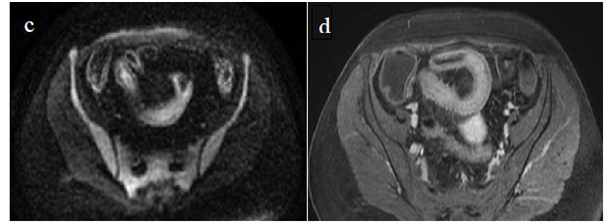

Figure 4 (a) Coronal SSFSE (singleshot fast spin echo) T2-weighted image with fat suppression (b) axial FIESTA (fast imaging employing steady-state acquisition) image show wall thickening (white arrow) and stenosis of the lumen in the terminal ileum. Note the prestenotic dilatation in b (white arrowhead). (c) Neoterminal ileum wall is thickened and has high signal on diffusion-weighted (DW) image (b= 800 s/mm2) (white arrow) and dark signal (black arrow) on the apparent diffusion coefficient (ADC) map in (d) indicating restricted diffusion. (e,f) ADC value measurement from the wall of the terminal ileum on magnified DW image. (e) and corresponding ADC map (f): ADC value = 1.20 × 10-3 mm2/s

Figure 5 Comparison of coronal (a) and axial (c) DWI sequences with the respective

after contrast medium injection (b, d).